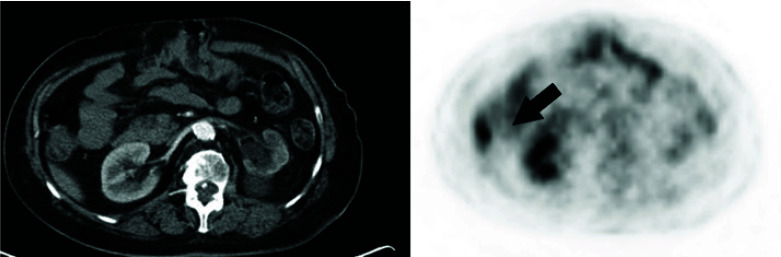

Immunotherapy has revolutionized the treatment landscape for solid tumours. Here, we describe the case of a 69-year-old woman with advanced endometrial cancer (EC) who achieved prolonged disease control with immunotherapy. The patient was diagnosed with stage IIIC EC in February 2020 and was treated with carboplatin and paclitaxel, followed by radiotherapy. Relapses occurred in February 2021 (treated with doxorubicin and palliative radiotherapy) and July 2022 (treated with a carboplatin rechallenge). Pembrolizumab and lenvatinib were started in November 2022. Although the initial scan showed progressive disease, restaging 2 months later showed stable disease, which was maintained on pembrolizumab and lenvatinib until progression in October 2024. This article is part of the New treatment options for advanced endometrial carcinoma Special Issue: https://www.drugsincontext.com/special_issues/new-treatment-options-for-advanced-endometrial-carcinoma.

Abstract Image